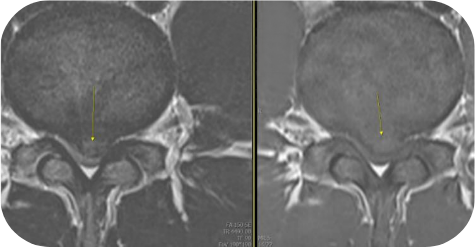

PELD

척추내시경

이 수술법이 처음 나온 지는 20년이 넘었습니다만 최근 들어 기기와 기술의 발전으로 각광을 받게 되었습니다. 피부에 약 7 mm 크기의 내시경을 넣어 수술을 하는 것으로 수술 후 회복이 매우 빠르다는 장점이 있습니다. 과거에는 터져 나온 디스크를 처리하지 못하는 한계를 보였으나 이제는 많이 발전하여 디스크의 여러 유형을 처리할 수 있어 수술의 성공률이나 환자의 만족도도 많이 높아졌습니다.

- 추간판탈출증